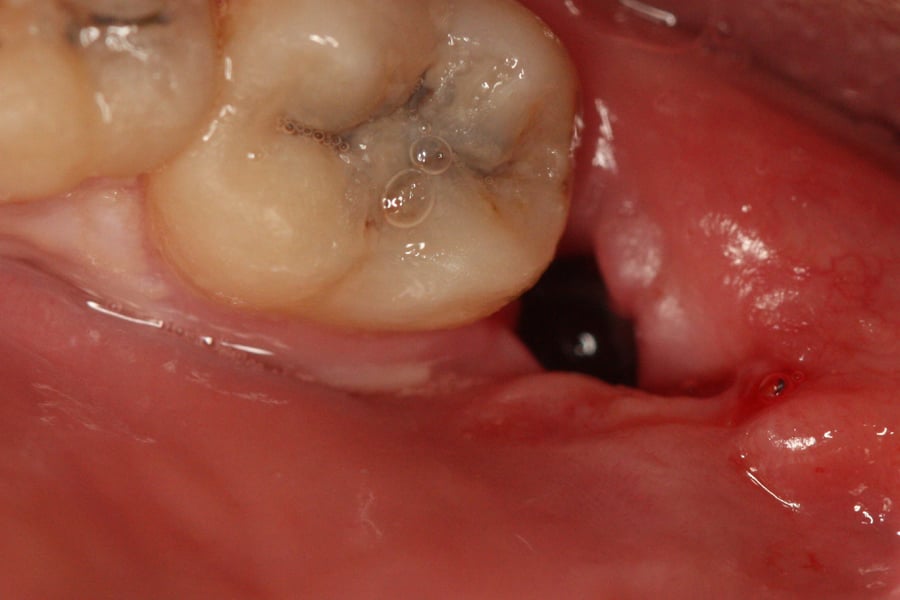

Suchy zębodół (ASD) jest to proces zapalny rozwijający się w 2-3 dobie po zabiegu ekstrakcji zęba wskutek zapalenia zakończeń nerwowych, zakażenia bakteryjnego wywołanego nieuformowaniem się, rozpadem lub usunięciem skrzepu, pełniącego funkcję naturalnej bariery ochronnej.

Objawy:

– silny ból

– niezmienione zapalnie otoczenie zębodołu

– wrażliwe na dotyk dno i ściany zębodołu